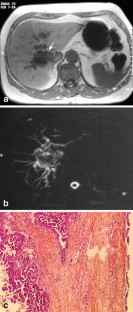

Magnetic resonance imaging (MRI) and magnetic resonance cholangio-pancreatography (MRCP) features were analyzed in the diagnosis of seven surgically resected hepatobiliary cystic tumors with reference to histopathological data. Homogeneity, size, location, signal intensity, presence or absence of septa and/or nodules and MRCP features of the lesions were studied. Histological evidence demonstrated six biliary cystadenoma (BCA) including four pseudo-ovarian stroma (POS) and one biliary cystadenocarcinoma (BCAC). Cystic lesions (3–15 cm in diameter) were homogeneous in the six BCA, heterogeneous in the one BCAC, and were located in the left and right liver, respectively. On T2-weighted images all lesions were hyperintense. On T1-weighted images hypointensity was found in three BCA (all serous fluid, including one POS), isointensity was found in the three others (two mucinous and one hemorrhagic fluid, including three POS) and in the one BCAC (containing mucinous fluid). Septas were present in all cases and nodules only in the one BCAC. On MRCP a hyperintense cystic lesion was found in all cases and a bile ducts dilatation in two BCA and the one BCAC. Gadolinium-enhanced MRI in combination with MRCP is a valuable tool for the diagnosis of BCA or BCAC. However, no specific information is gained for POS detection.

Fig. 2